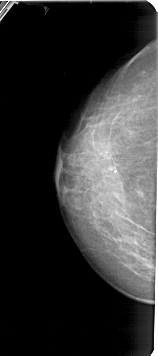

A_1425_1.LEFT_CC

LEFT_CC LINES 5326 PIXELS_PER_LINE 2356 BITS_PER_PIXEL 12 RESOLUTION 43.5 NON_OVERLAY